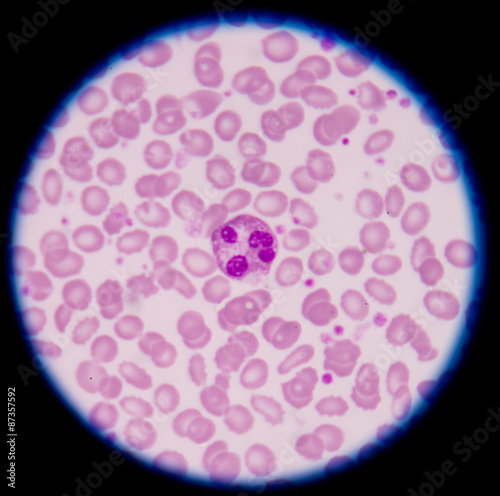

Mikrofotografi - Plakater, Poster, Billeder på lærred